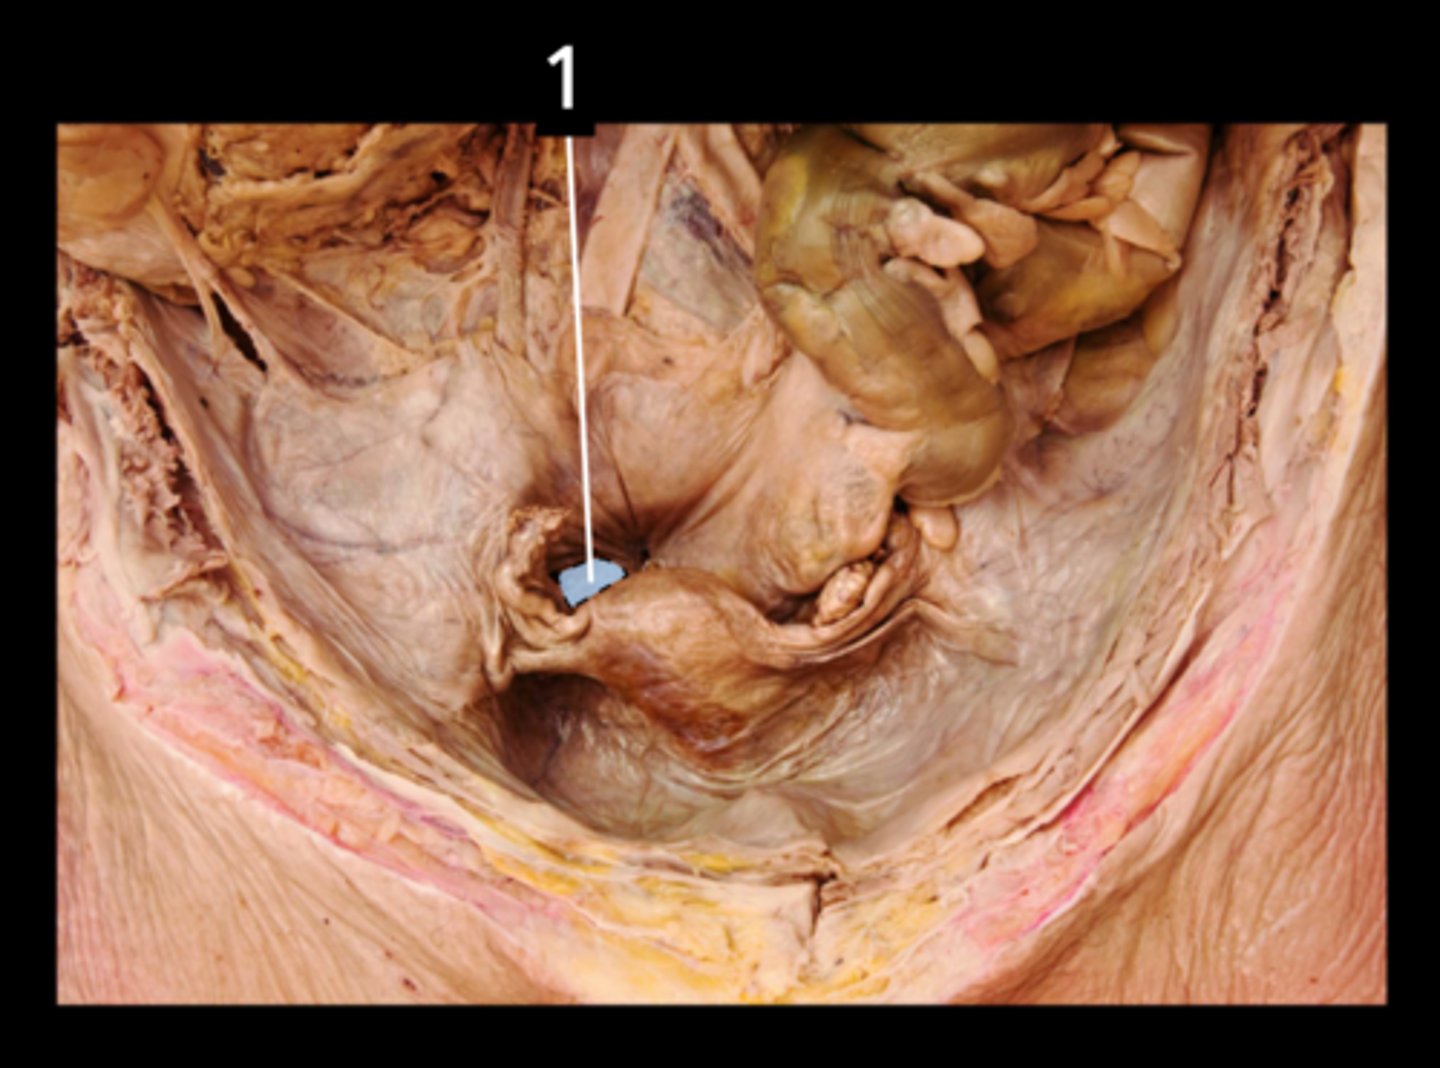

Rectum

Anal Canal

Internal Anal Sphincter

External Anal Sphincter